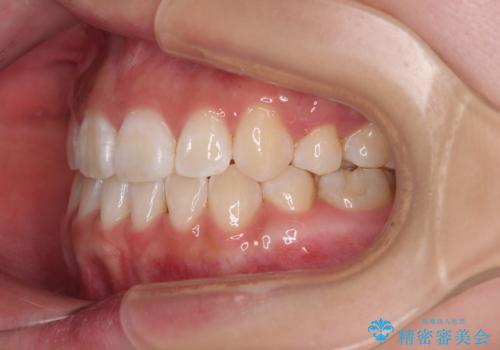

上下非接触の前歯 口元の突出感を改善する抜歯矯正

- 口元の突出感と上下前歯のズレを気にして来院された患者様です。

舌の突出癖により上下の前歯は非接触となっている状態でした。

舌のトレーニングをしっかりと行ってくださり、1年半という非常に短い期間で仕上げることができました。